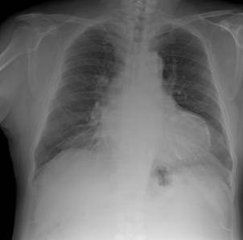

1.吸入性肺炎病變部位大多位於右葉後上方或下葉後方呈現沿肺段均勻分布的大片濃密模糊炎性陰影邊緣不清多單發節段分布也可多發小彈片狀陰影通常位於肺周邊部貼近胸膜類似一般肺炎1~2周后組織壞死形成膿腫發展成壞死性肺炎

2.壞死性肺炎主要表現為在緻密肺段實變陰影中迅速形成空洞直徑<2cm病變不只侵犯一葉肺

3.急性肺膿腫表現在大片濃密的陰影中出現圓形透光區空洞呈圓形內壁光滑其內見液氣平面治療得當實變陰影與空洞逐漸縮小消失或殘留索條影

4.慢性肺膿腫X線差異較大膿腔壁較厚內壁不規則空洞大小形態不一可伴有液平面周邊有纖維索條影並有不同程度的肺葉收縮治癒好轉者有半數繼發支氣管擴張

5.血行播散所致者為在一肺或兩肺邊緣部多發的散在小片狀炎性陰影或邊緣較整齊的球形病灶其中可見膿腔及液平面

6.膿胸的表現依積膿量的多少而有所差異患側胸部出現大片濃密陰影若伴有膿氣胸可見液平面